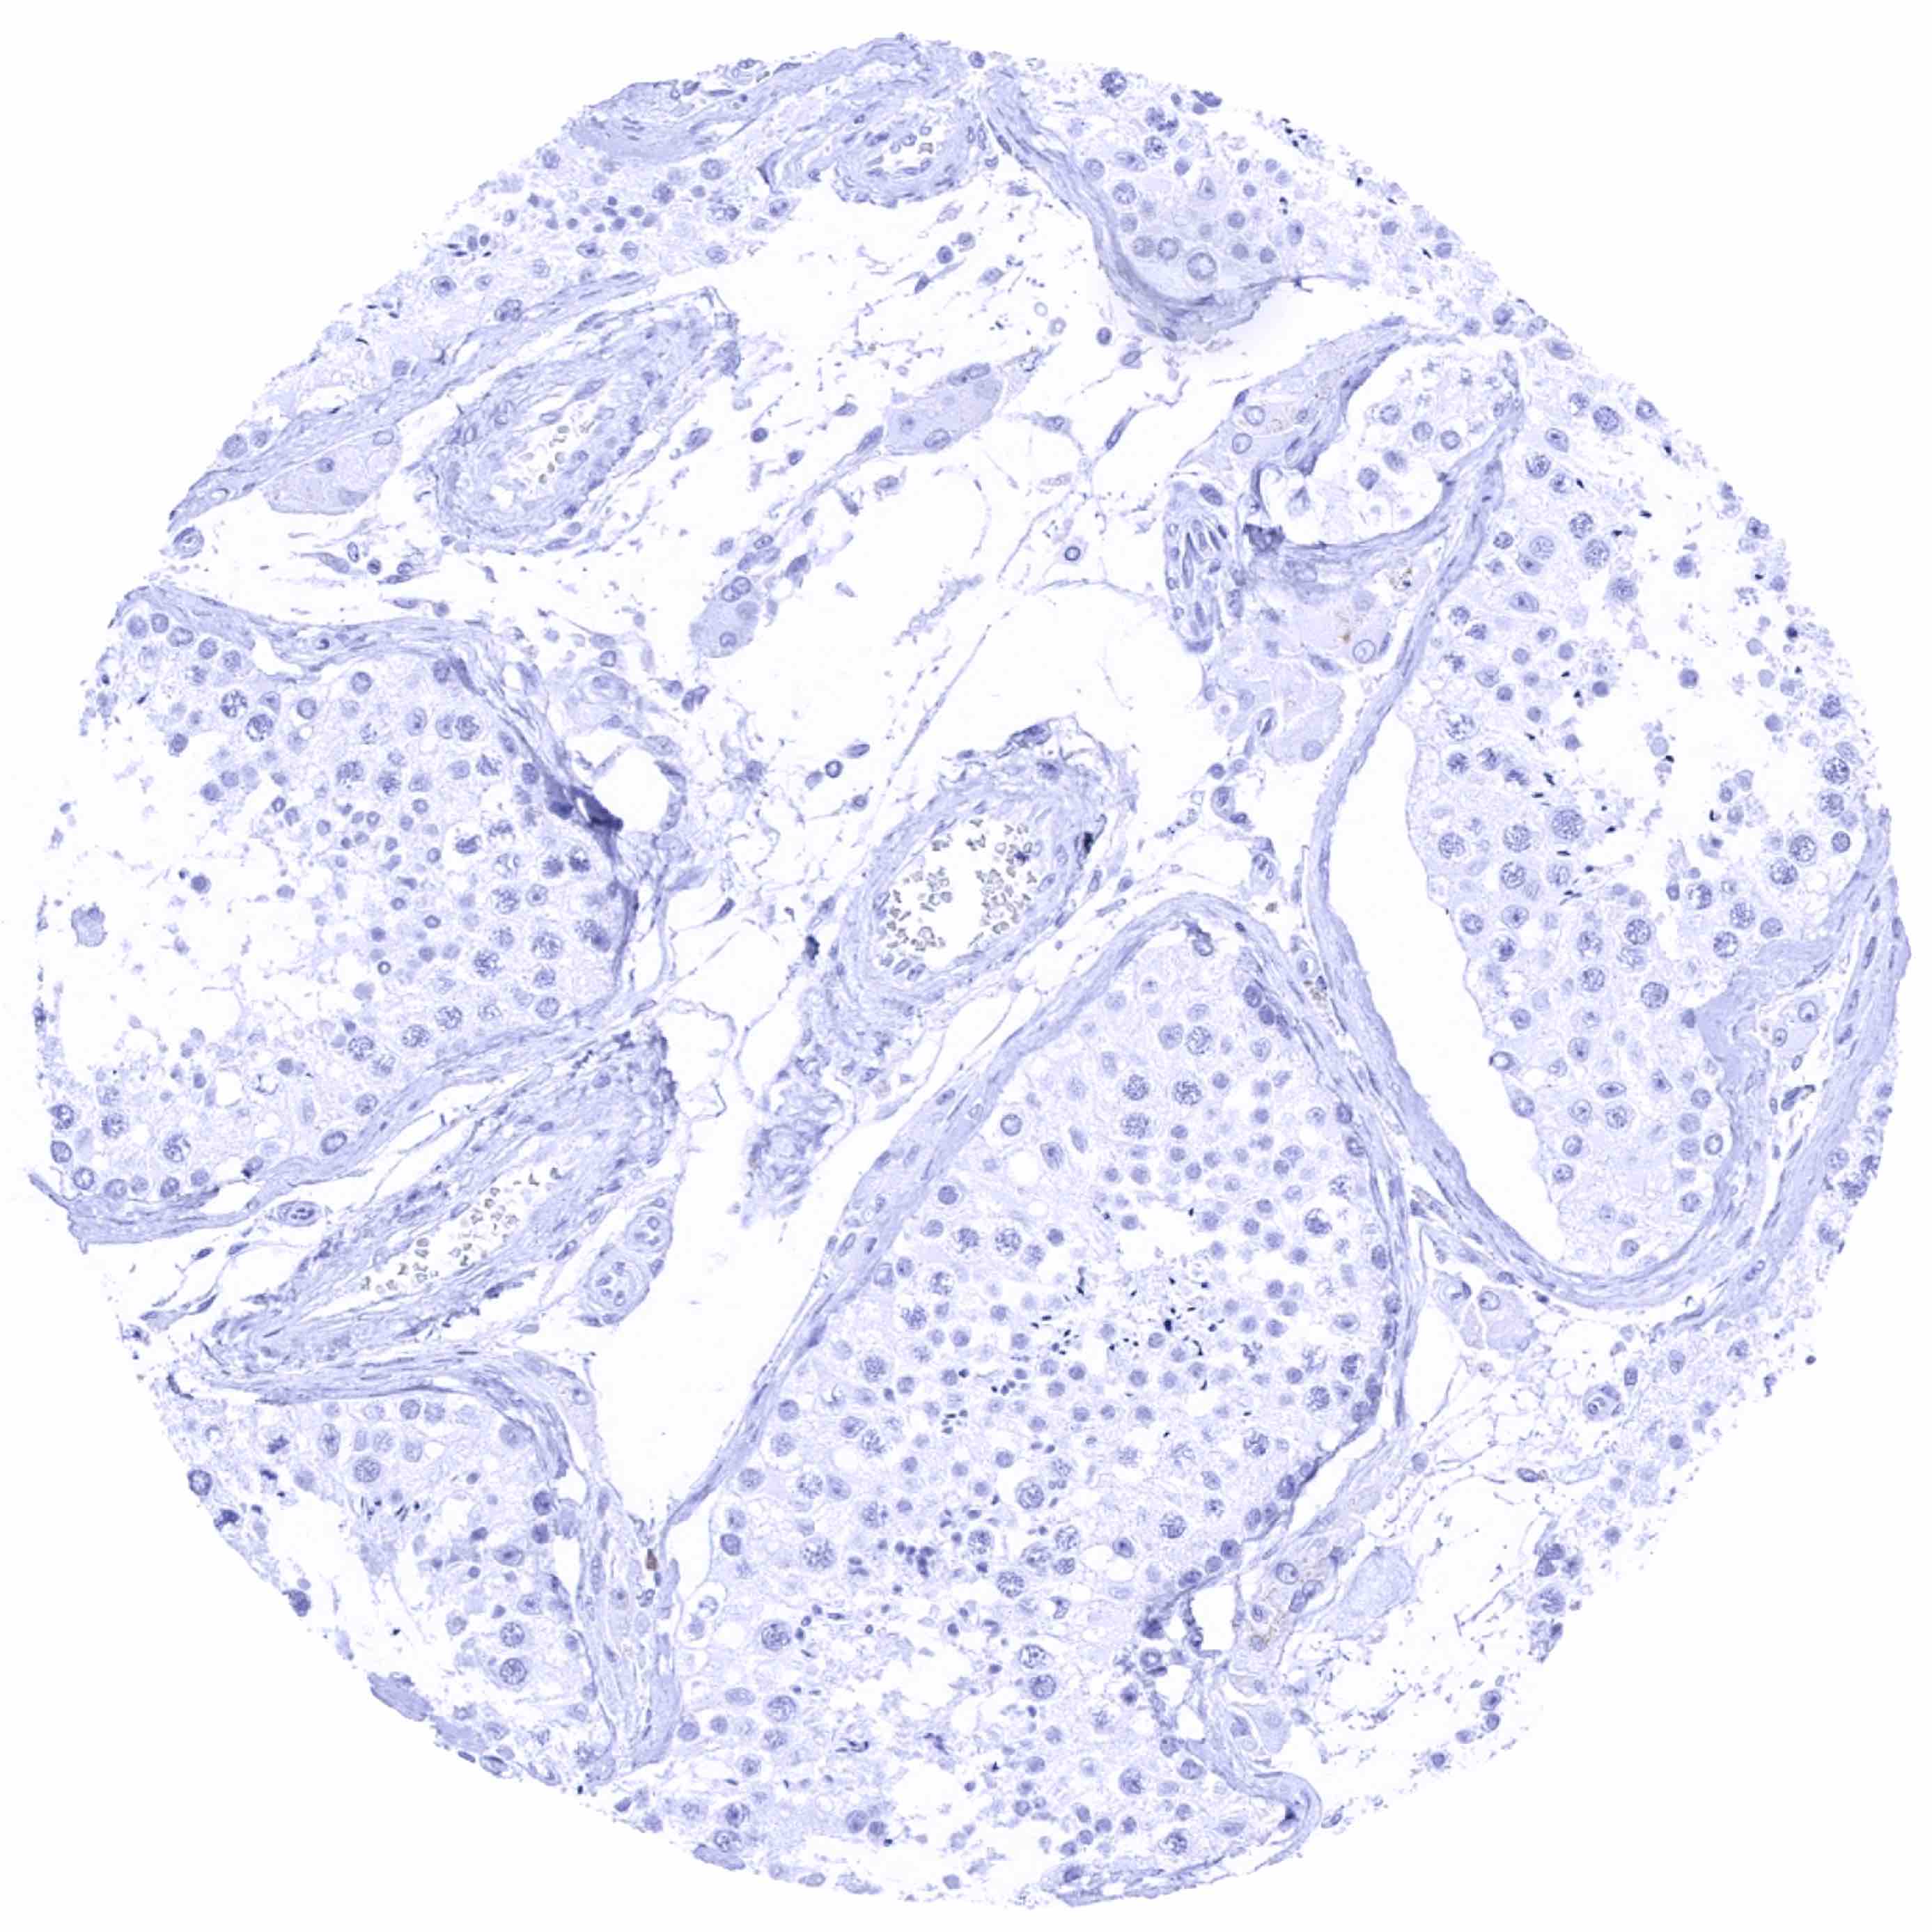

Testis